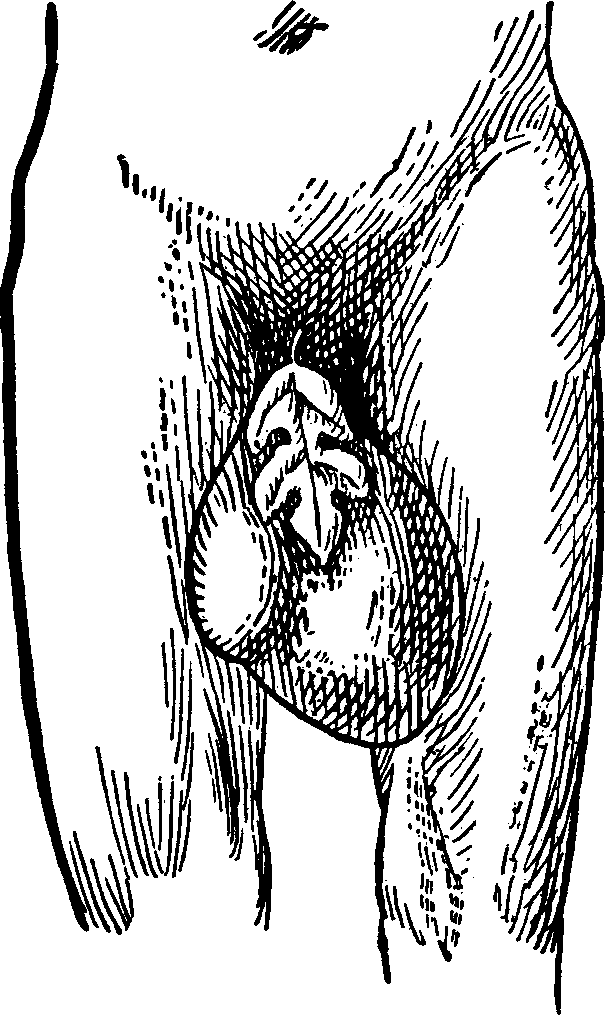

It occasionally happens that the hymen is entire, or imperforate, at birth. This may not be discovered before puberty. But when this period arrives and the menstrual discharge takes place into the vagina, the female will suffer from the retention and accumulation of this secretion, and ultimately a tumor or a protrusion of the membrane which closes the vagina will occur, giving rise to severe pain and other serious symptoms. The retained menstrual fluid, increasing in quantity at every monthly period, dilates the womb as well as the vagina, and even the Fallopian tubes become distended, presenting at length an urgent necessity for relief.

Treatment. This condition admits of relief only by operative surgery. The operation consists in dividing the hymen by a crucial incision, thus allowing the accumulated fluid to be discharged, after which the vagina is cleansed by syringing it with warm water.